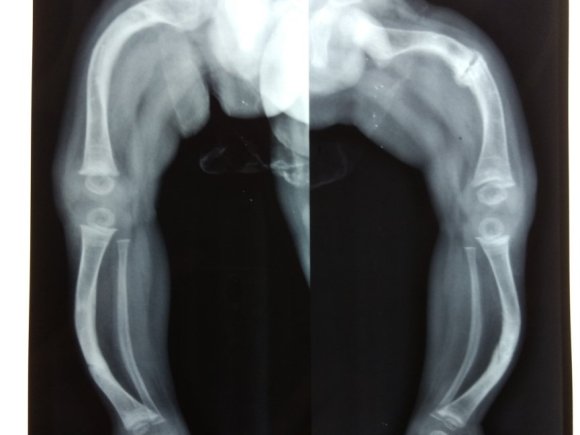

Developmental Dysplasia of Hip - Left hip is dislocated

Developmental Dysplasia of Hip – Left hip is dislocated